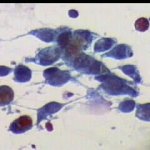

Εικονες φυσιολογικών και παθολογικών κυττάρων ενδοτραχήλου κι ενδομητρίου στο επίχρισμα κατά Papanicolaou. Περιστατικά ιατρείου. Παρατίθενται για τις ανάγκες επίδειξης περιστατικών στο forum του www.gyn.gr, για φοιτητές εργαστηριακών παραϊατρικών επαγγελμάτων και για καθε άλλο ενδιαφερόμενο.